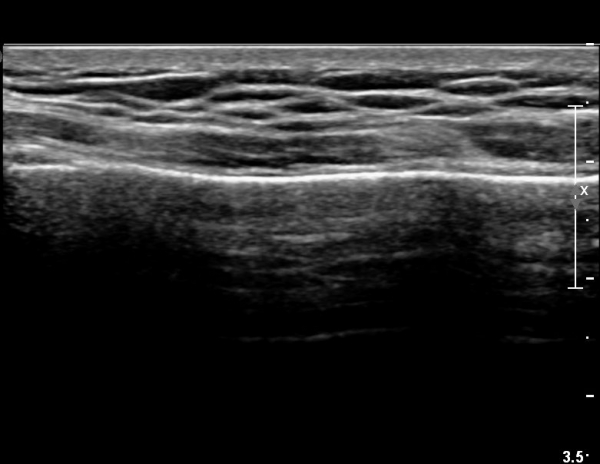

Á¶±Ý ´õ ¸»´ÜÀ¸·Î À̵¿ÇÏ´Ï Äá¾Ë»À ÇÇÁú°ñ ¿¬¼Ó¼º ¼Ò½ÇÀÌ °üÂûµÊ(»çÁö 3),